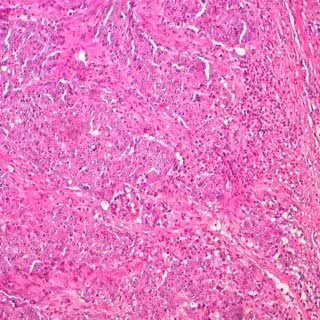

UCM - Archivo